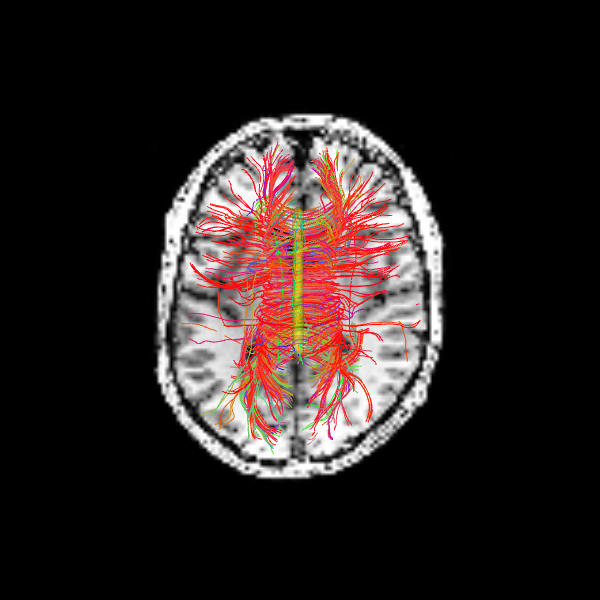

Let’s visualize the Corpus Callosum using deterministic maximum direction getter:

scene = window.Scene()

scene.add(actor.line(streamlines_det, colors=colormap.line_colors(streamlines_det)))

window.record(scene=scene, out_path="tractogram_deterministic.png", size=(600, 600))

Image('tractogram_deterministic.png')

The following alternative visualizations display the corpus callosum streamlines overlaid on T1-weighted anatomical slices (axial at z=35 and sagittal at z=35), with the seed ROI shown as a semi-transparent yellow contour.